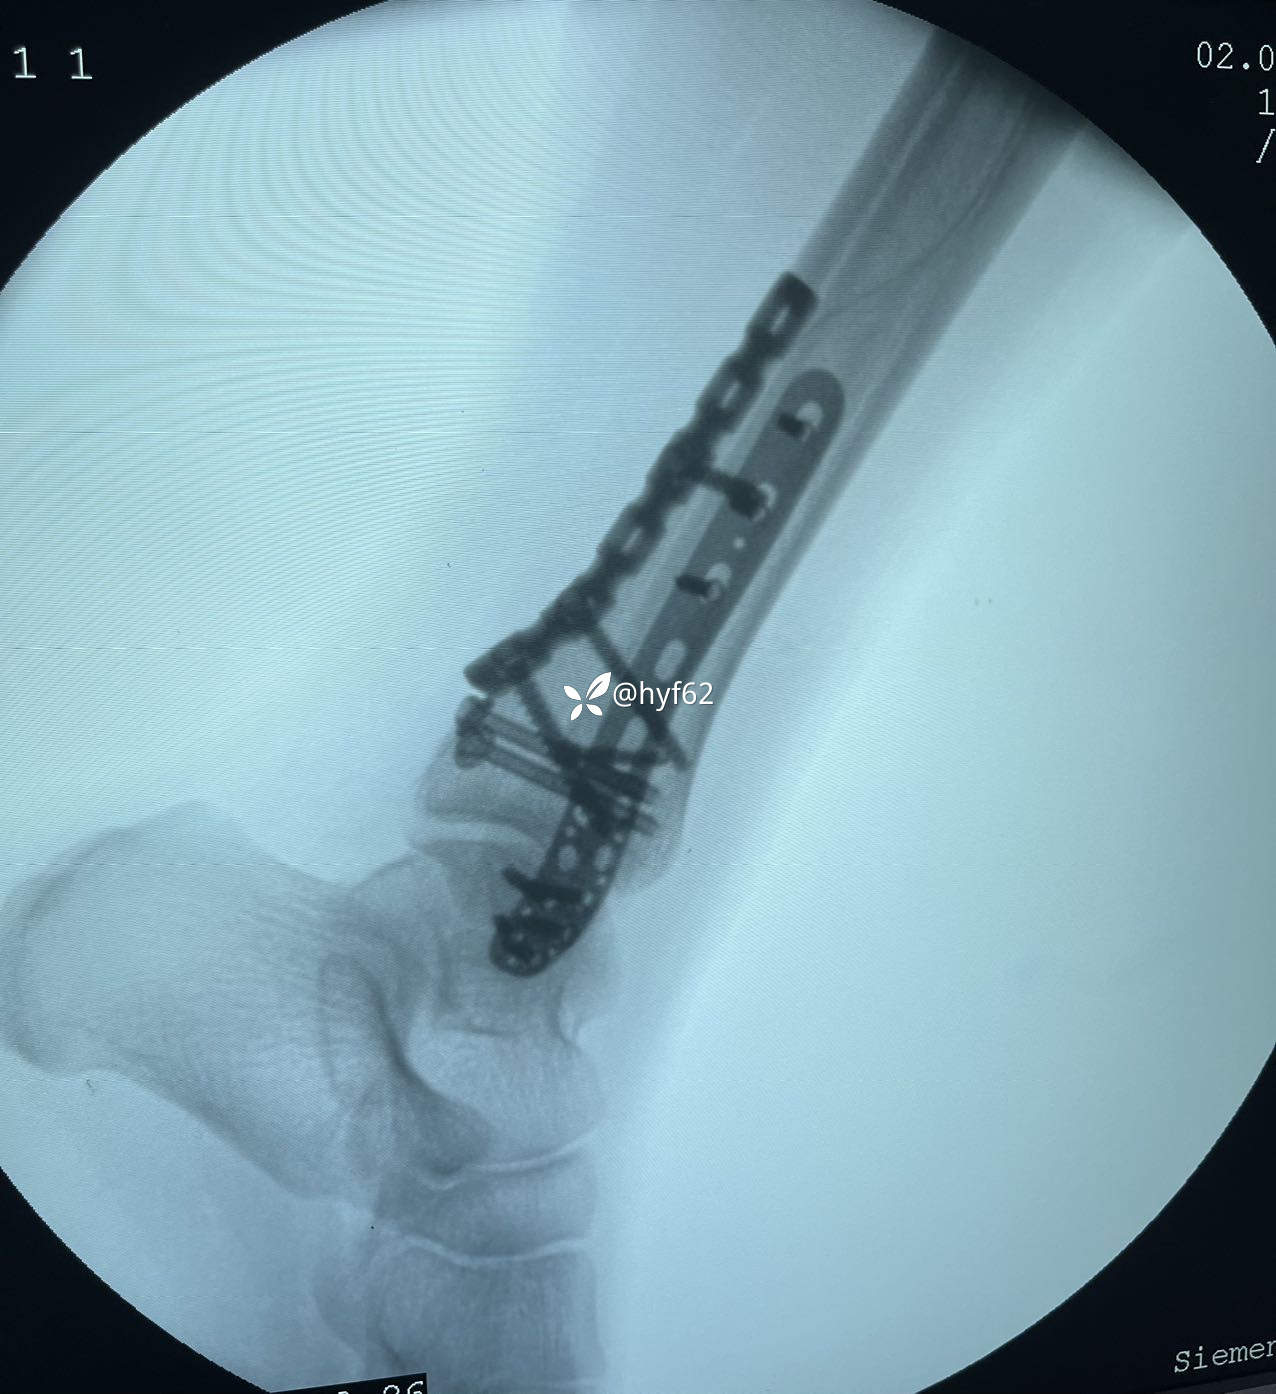

右外后踝骨折,急诊手术没做MRI,如何判断三角韧带损伤?!

诊断:右外后踝骨折,三角韧带损伤?

没有后侧解剖板,有啥用啥!

讨论:1分型?

2受伤机制?

3内踝需要探查三角韧带吗?

4后侧骨块固定方式有哪些,如何选择?!